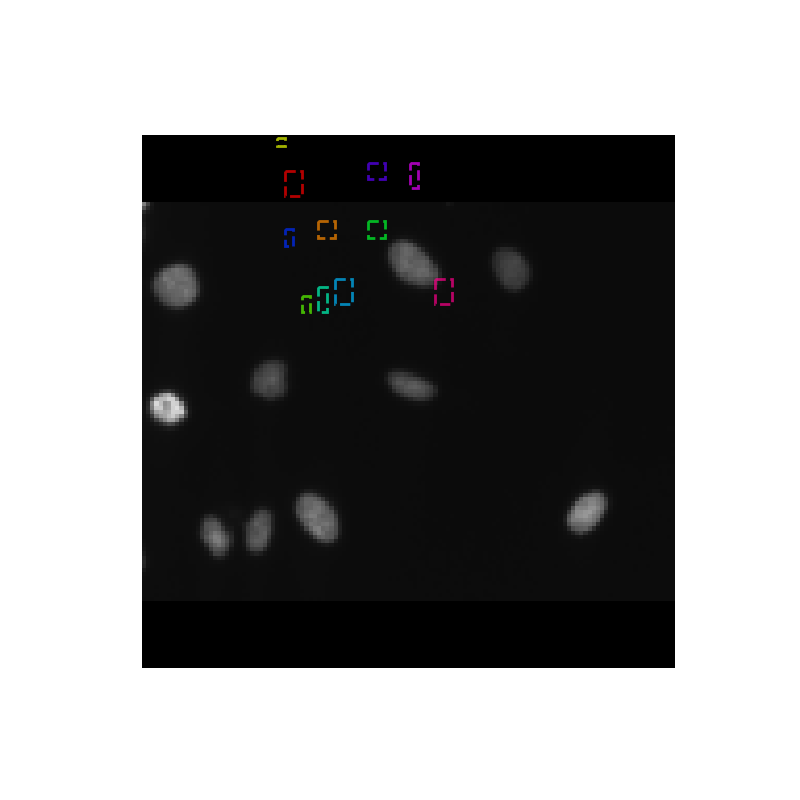

Our tool takes images of a collection of cells under different conditions as input and produces an image with bounding boxes and masks highlighting individual nucleus as output.

We finally used Mask Regional Convolutional Neural Network to come up with candidate region proposals and train the network to select the most probable regions in the image that contain a nucleus.